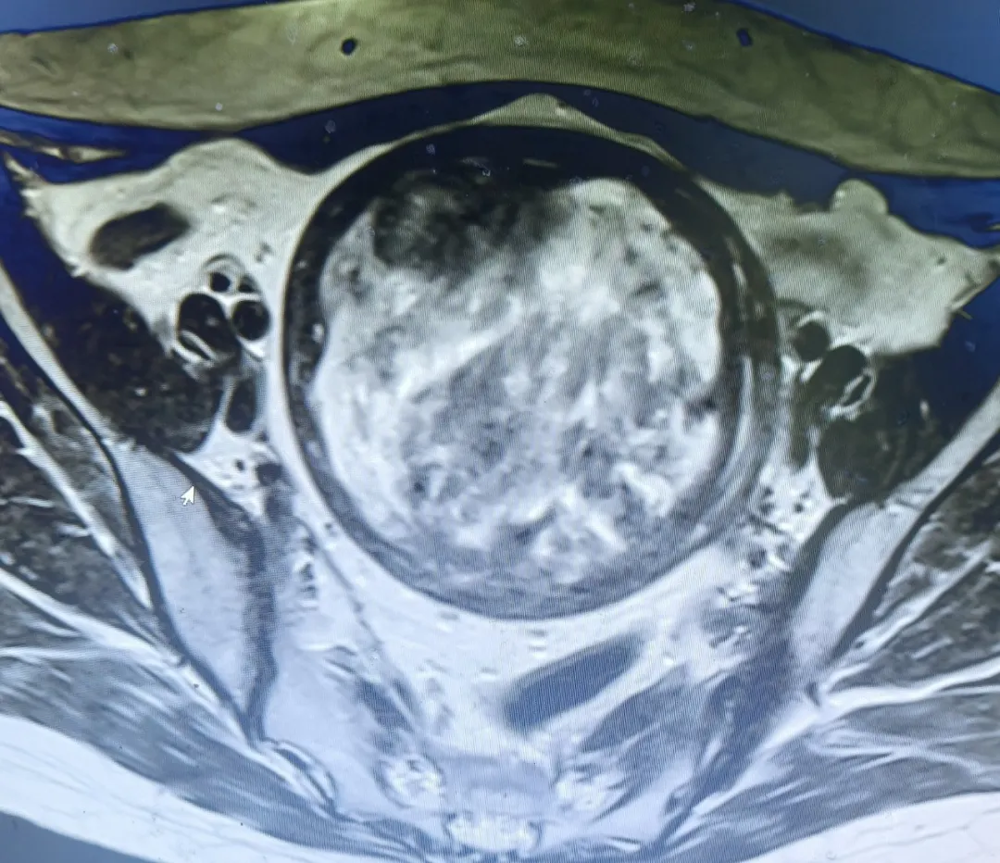

案例回顾:51岁陈女士半年前发现腹部包块未重视,近期因月经量增多来院就诊。妇科团队接诊后迅速为陈女士完善相关检查,彩超和核磁共振结果显示,子宫已增大至孕4+月大小,后壁显现一枚肌瘤尺寸约117mm×107mm×103mm,确诊巨大子宫肌瘤伴变性可能,手术指征十分明确。

手术前后对比图

手术前